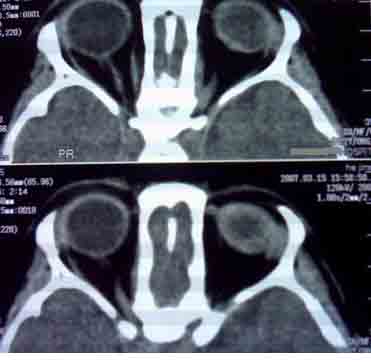

患者,偶然发现左眼无光感,平时,无明显不适,眼外观无明显异常。

首先考虑视网膜母细胞瘤。

支持左侧视网膜母细胞瘤,可惜没有钙化。

大家有没有想到有哪些需同成视网膜细胞瘤鉴别诊断的疾病?正是没有钙化,所以此病首先更应该考虑什么?请大家说说看。

考虑左侧眼球渗出增殖性视网膜炎所致视网膜剥离,建议mri检查。

1.ct表现:眼球内均匀高密度肿块,有增强,并多有点状或团块状钙化,在3岁以下的儿童有极大的诊断价值。可见相关视网膜下积液。

2.mr表现:肿瘤t1加权像为较视网膜略高或与视网膜相等的信号强度,t2加权像为低信号强度。大钙斑t1、t2加权像均为低信号斑,小钙斑不易显示。视网膜下积液或积血显示清楚。

鉴别诊断 :需与渗出性视网膜病鉴别。